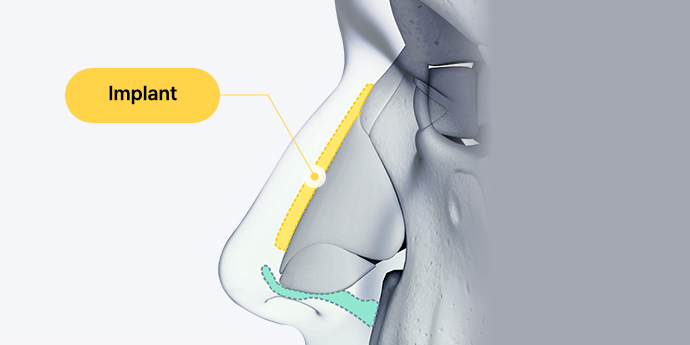

Nose Bridge(Implant)

Design the height and shape of the nose

by considering the face shape,

nose structure,

the distance and length between the eyebrows,

and the forehead line, then insert a biocompatible

custom implant

to elevate the nasal bridge.

Nose Tip (Autologous Cartilage)

Use autologous cartilage to refine the nose tip,

minimizing foreign sensation while

ensuring a natural line and soft, smooth texture.